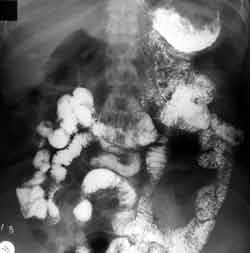

Рис. 1. Состояние после резекции дистального отдела желудка с формированием анастомоза конец в конец. Расширение начальных отделов тощей кишки вблизи культи желудка. Ускоренная эвакуация приводит к перерастяжению контрастной массой проксимальных отделов тощей кишки.